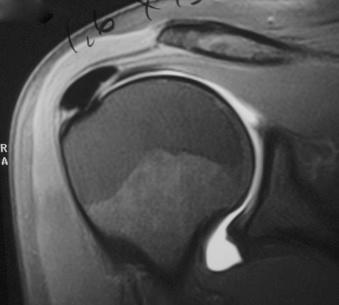

The shoulder is often swollen, and the overlying skin is sensitive to touch. The slightest pressure applied over the supraspinatus insertion may elicit severe pain. Active and passive range of motion is painful and restricted. Another cause of acute shoulder pain is cervical radiculopathy, and the surgeon should attempt to elicit a history of radicular pain or paresthesia, and carefully examine the patient for neck pain with neck motion. A review of the radiographs confirms the diagnosis. Owing to the persistent, severe pain, patients often present with a magnetic resonance image taken to evaluate the rotator cuff tendons. Diagnostic ultrasonography is an easy and effective method of diagnosis ( Figs. 16.6 and 16.7 ).

FIGURE 16.6, Magnetic resonance imaging of calcific tendinopathy.